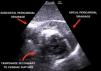

A 62-year-old woman with no personal history of disease was seen due to epigastric pain lasting four days, suffering a right-side pure hemi-motor lacunar stroke with anodyne multimodal CT findings. The ECG tracing evidenced inferior ST-segment elevation with Q waves, and the patient was admitted to intensive care. Transthoracic echocardiography showed septal-basal interventricular communication (IVC) presenting an akinetic inferior aspect with thinning and hyperechogenicity suggestive of pseudoaneurysm with possible contained myocardial rupture (Fig. 1, Video 1). Emergent surgery was discarded due to the neurological condition of the patient and surgical risk due to friability of the tissues. While in wait for the final decision, a cardiac MRI was performed (Fig. 2), after which the patient suffered cardiac arrest with pulseless electrical activity secondary to tamponade, with futile resuscitation efforts (Fig. 3, Videos 2 and 3). Mechanical complications following acute myocardial infarction, while unusual nowadays, remain a potentially fatal and time-dependent disorder in which imaging techniques such as echocardiography continue to play a key role.